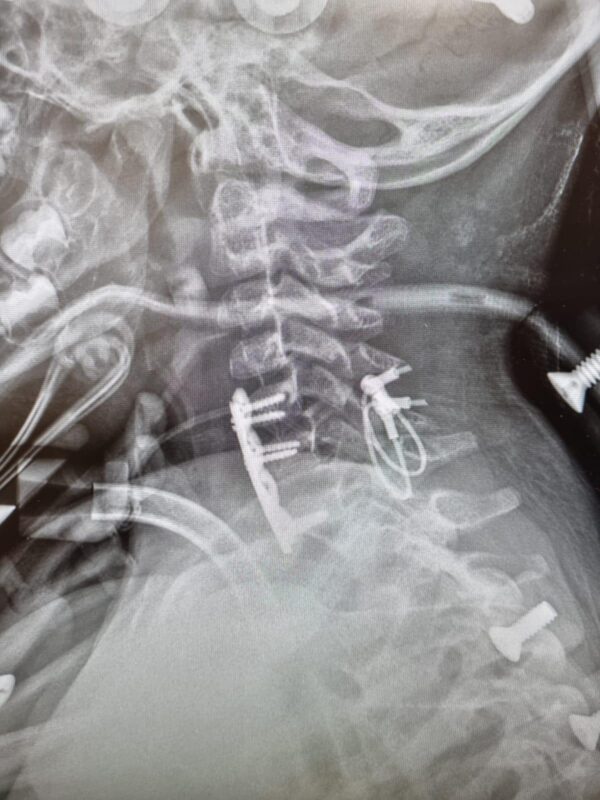

"היפרדות מלאה בין החוליות הצוואריות עם התרחקות של מעל 2 ס״מ, היא פגיעה אשר נדיר מאוד שמטופל ישרוד אותה". מסביר ד"ר ארזי. "התייעצנו עם מספר מומחים מהארץ ומחו״ל ואספנו דעות שונות לגבי אפשרויות הטיפול השונות. לציין שלאף אחד מהמומחים לא היה ניסיון עם מקרה כזה בדיוק. מאחר ופגיעה מסוג זה נדירה כל כך, לא קיימת מערכת לקיבוע ע״ש צווארי בילדים כל כך קטנים".

לאחר דיון מעמיק שביצע ד"ר ארזי יחד עם מומחי עמוד שדרה מרחבי העולם, הוחלט לבצע ניתוח בגישה כפולה קדמית ואחורית כאשר מאחור, נעשה שימוש במערכת ייעודית של כבלים גמישים לעמוד השדרה ומלפנים בשתי פלטות קטנות שמיועדות בד״כ לקיבוע שברים בלסת.

"במהלך הניתוח יכולנו לראות את חוט השדרה עצמו שנראה פגוע מאוד. הניתוח עבר בהצלחה ובסיומו קיבענו אותו בהלו-וסט (זו המסגרת שמחזיקה לו את הראש) כדי לשמור על הקיבוע הפנימי בפציעה הקשה. כשראיתי את עמרן מזיז את הידיים התרגשתי מאוד. סיכוייו לחיות לאחר פגיעה מסוג זה היו נמוכים לא כל שכן להזיז את ידיו. צפויה לו דרך ארוכה ומאתגרת שתכלול שיקום נשימתי ובהמשך שיקום תפקודי. אני שמח שהצלנו את פלג גופו העליון ומקווה שמצבו ילך וישתפר".